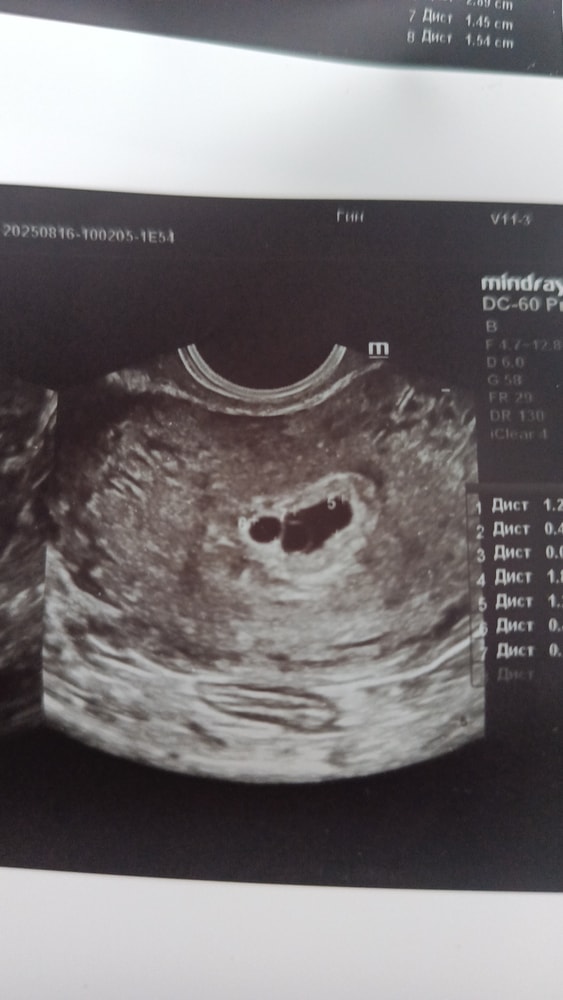

Татьяна, вот так , только еще дальше у меня. Фото не мое-нашла в интернете. Мне фото с двумя не делали. Только по отдельности каждое плодн яйцо сделали.

Анастасия, ну тут точно диди. Даже сомнений быть не может. И размеры практически одинаковые, мне кажется, все хорошо должно быть.